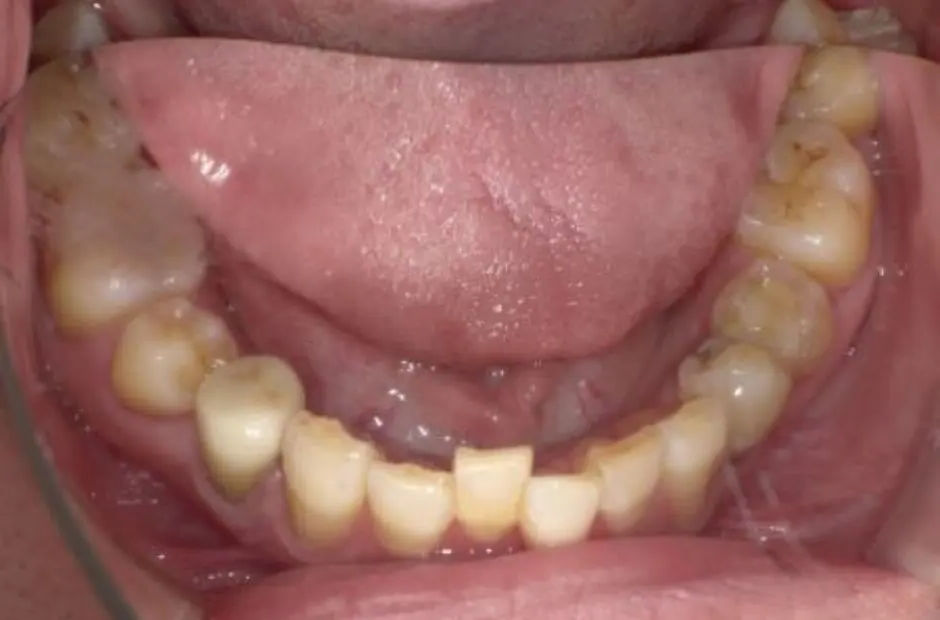

case.02

金属アレルギー治療の症例・治療前写真(銀歯7本)

金属アレルギー治療の症例・治療後写真(銀歯7本)

「 メタルフリーで、健康を手に! 」

当サロンのメタルフリー治療は、金属アレルギーの心配を排除し、健康な口内環境を実現します。高品質な非金属素材で安心と健康を手に入れましょう。

治療内容 古い銀歯を取り除き、レジンとセラミックを組み合わせて装着

治療期間/回数 2ヶ月/通院6回

費用 220,000円(税込)(検査・診断、手術関連処置費用、レジン装着の費用等は含まない)e-maxインレー:55,000円/1カ所

リスク/副作用 咬合による割れ